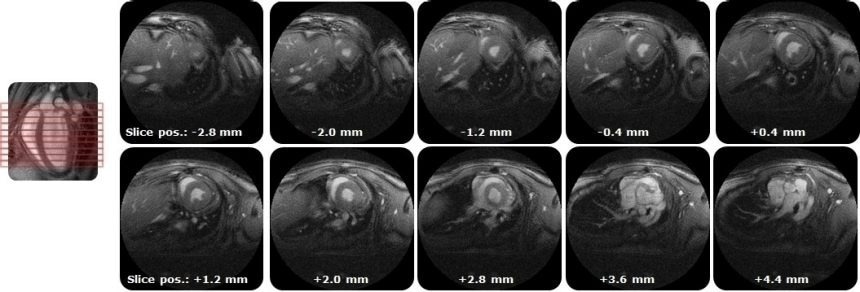

- Fully automated PET/CT stitched protocol, including attenuation correction (AC) map for rats up to 250 mm in length

Fast extended PET/CT imaging for full rat body coverage. Image Credit: Bruker BioSpin Group

IntraGateUTE, with its radial readout, enables high-quality cardiac cine data in shortest measurement time. Image Credit: Bruker BioSpin Group